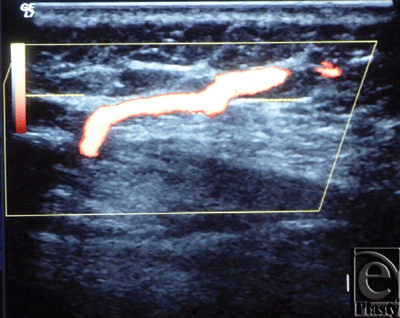

The site of the detectable perforator(s) was projected by a colored marker on the patient's skin so as to estimate the label remoteness (representing the perforation site) from the sternum (Fig 2), and the number of encountered perforators parasternally in each investigated space was counted as well. The inner diameter of each perforator was measured (Fig 3). Figures 4 to 8 show color duplex photos for perforators penetrating the fascia to reach the dermoglandular target.

| Figure 3. Color Duplex photo shows the diameter and depth of a certain visualized 5th internal mammary artery perforator from the skin surface. The point of measurement was at the perforation point. |

![]() |

| Figure 4. Color Duplex photo shows a 4th internal mammary artery perforator while perforating the superior surface of the pectoralis major muscle (the dashed line). |